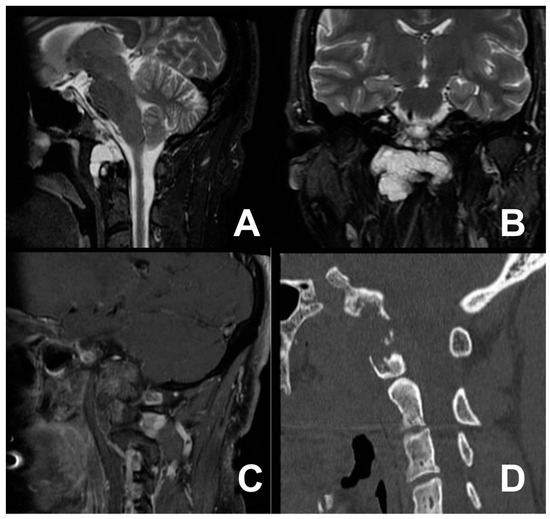

3.2. First Case: Two-Staged Submandibular Retropharyngeal and Endoscopic Endonasal Approach